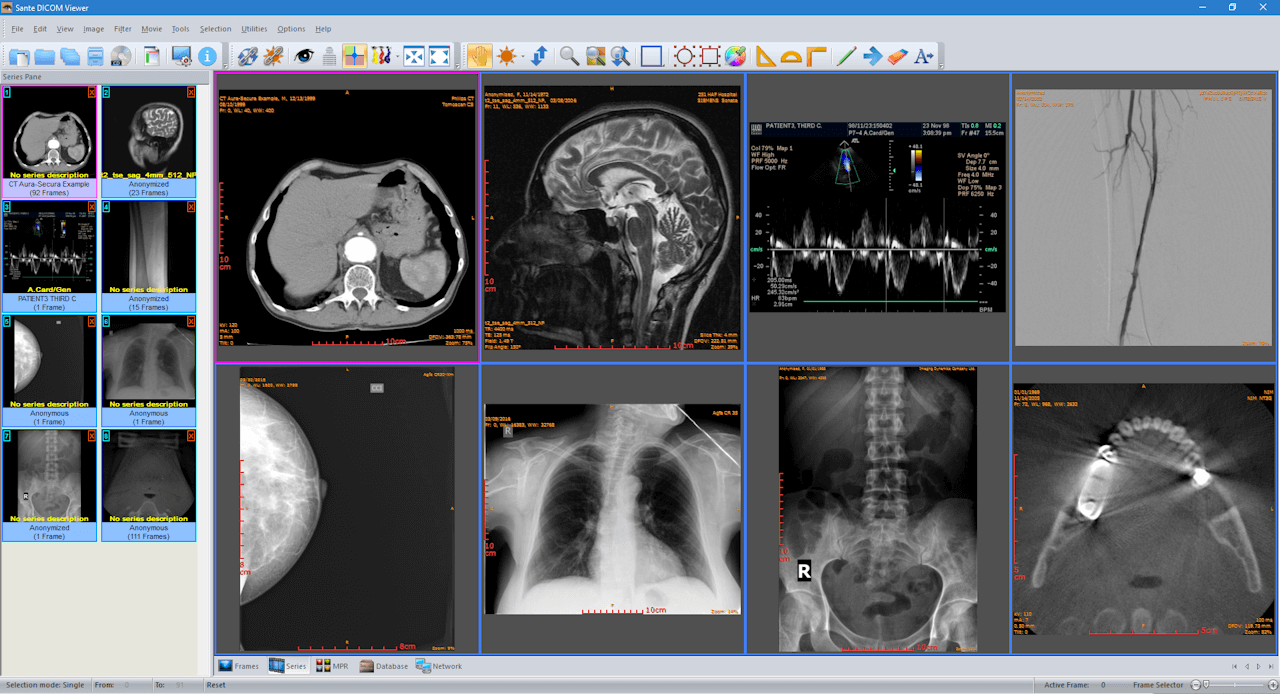

| 12. | Sante | Windows | Mini-PACS available | Y | N | N | Picture, movie and data files | 100 MB | Intel Core i3/ 2 GB RAM; Screen resolution 1064x768, true color | Free for 45 days only |